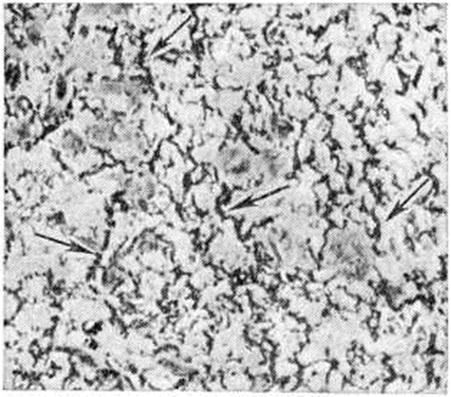

Рис. 1.

Микропрепарат слизистой оболочки толстой кишки при дизентерийном катаральном колите: выражены очаговые поражения и лейкоцитарная инфильтрация (указано стрелками); × 40.